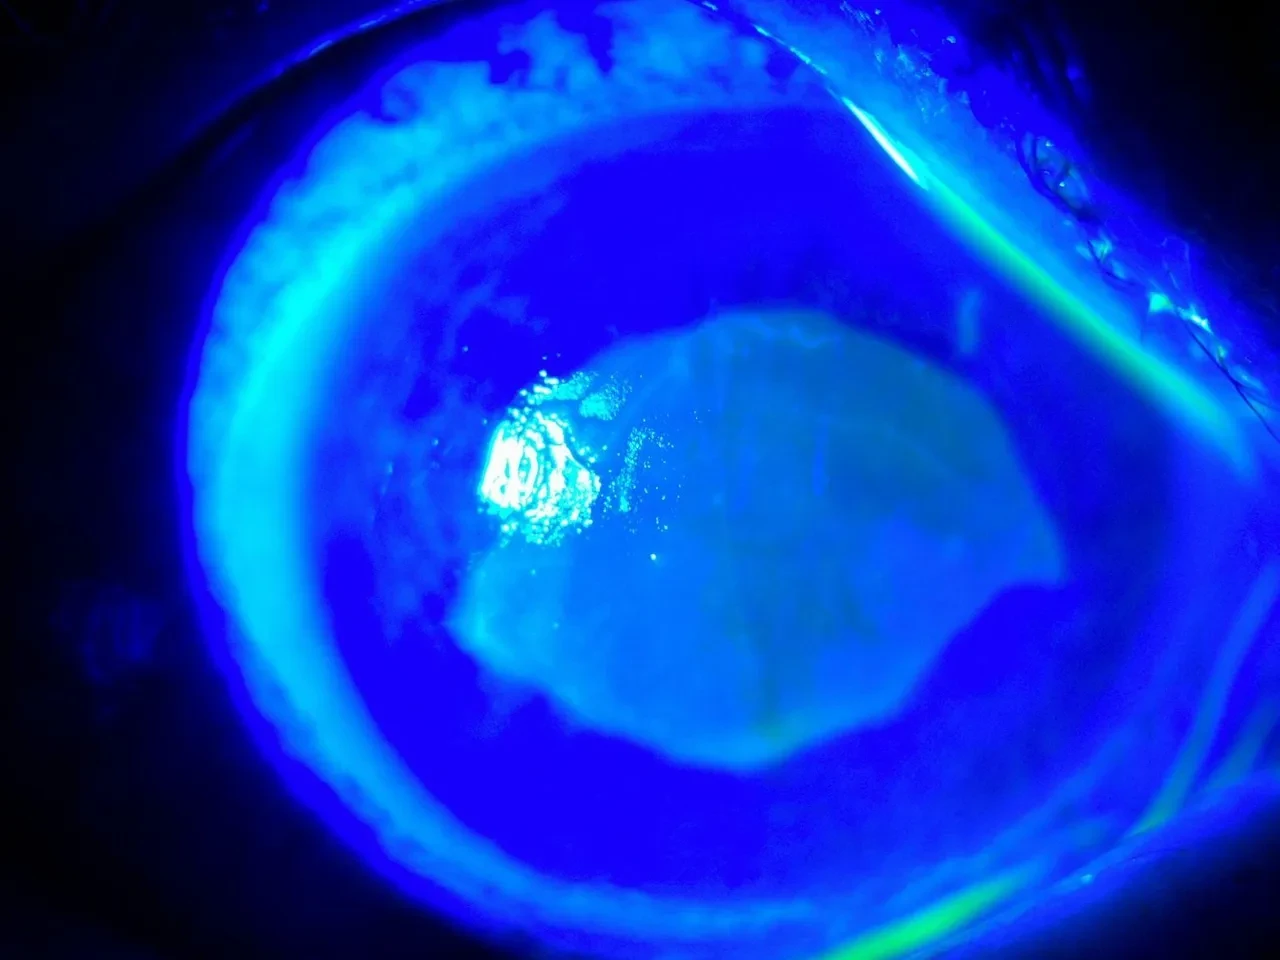

Göz Hastalıkları Uzmanı Doç. Dr. Ömer Faruk Yılmaz ve ekibi hastaya müdahale ederken korneanın en dış katmanı olarak ifade edilen kornea epitelinin zarar gördüğü belirlendi. Göze yabancı cisim, kimyasal madde kaçması ya da enfeksiyon durumlarında gözü temizlemek amacıyla uygulanan göz yıkama tedavisi gerçekleştirildi. Yaklaşık 2 haftalık tedavinin ardından hasta sağlığına kavuştu. Doç. Dr. Yılmaz, hastasının yaşadığı süreç ve tedavisine ilişkin bilgi verdi. Yılmaz, hekim önerisi olmadan herhangi bir ürün kullanılmaması gerektiğine dikkat çekerek önemli uyarılarda bulundu. Öte yandan hastanın göz bebeğinin beyazlığı ve göz akının ise kızardığı hali fotoğraf karesine yansıdı.

Hastasına ilişkin bilgi veren Doç. Dr. Ömer Faruk Yılmaz, "52 yaşında bir bayan hastamız, kızının önerisiyle gözlükten kurtulmak için 2 gözüne taze kırlangıç otu suyunu sıkarak damlatmıştı. Kırlangıç otunu sıktığımız zaman sarı bir sıvı akmaktadır. Hastamız o sıvıyı her 2 gözüne damlatmış. İlk aşamada gözünde yanma, batma oluyor, birkaç saat sonra her 2 gözünü açamıyor, tamamen göremez hale geliyor. Bize geldiğinde hastamız 2 gözünü açamaz haldeydi. Göz muayenesinde 2 gözün korneasının tamamen tahrip olduğunu gördük. Korneanın epiteli tamamen soyulduğu için hastamızın gözünde pü şeklinde akıntı mevcuttu. Hasta, ‘Acaba göremeyecek miyim, gözüme ne oldu, bu ilacı neden damlattım?' diye sorgulayarak gelmişti" dedi.

"Kırlangıç otu kullandı, hastamız göremez hale geldi eğer tedavi edilmeseydi sonucun ne olacağını bilemiyoruz fakat tedavi sonucunda hastamız iyileşti. Gözlerinin fotoğrafını çektirdim, kırlangıç otunun geçişini gösterdik. Tedavi edilmediği zaman göz içinde belki de körlüğe ulaşabilecek şekilde istenmeyen yan etkilere yol açabilir. Yüzlerce farklı ot olabilir, yanlışlıkla faydalı bir ot damlatacağız diye zararlı bir otu damlatabiliriz. Göze direkt damlatılması steril değildir, göze zarar verebilir, enfeksiyon oluşturabilir. Faydalı bile olsa Sağlık Bakanlığı ruhsat vermeden, ilaç formatına dönüştürmeden, uygun dozajlar ayarlanmadan ve göz hekiminin önerisi olmadan göze herhangi bir bitkisel ilaç damlatılmasını önermiyoruz."